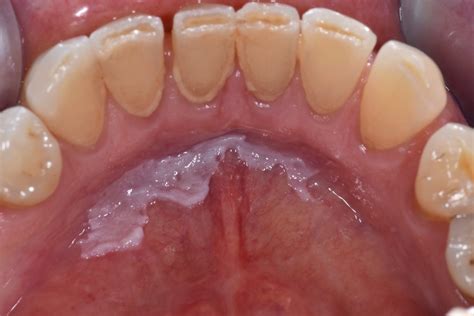

Leukoplakia on the lips is a condition characterized by the appearance of thick, white patches on the lips. These patches are typically painless but can be a cause for concern due to their potential to develop into cancer. Understanding the causes, symptoms, and treatment options for leukoplakia on the lips is crucial for early detection and effective management.

Leukoplakia on the lips refers to the development of white patches or plaques that cannot be scraped off. These patches are usually found on the inner surfaces of the lips and can vary in size and shape. The condition is more common in individuals who smoke or use tobacco products, as well as those who consume excessive amounts of alcohol.

Leukoplakia on the lips often presents with the following symptoms:

• Thick, white patches or plaques on the lips that cannot be scraped off.

• Patches that may be slightly raised or have a rough texture.

• Patches that can be painless or cause discomfort, especially if they become inflamed or infected.

• In some cases, the patches may develop into ulcers or sores.